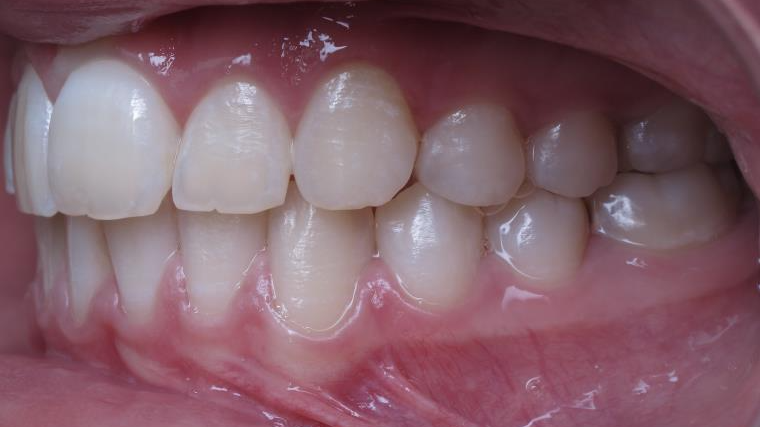

sectionnel multibagues pendant 25 mois